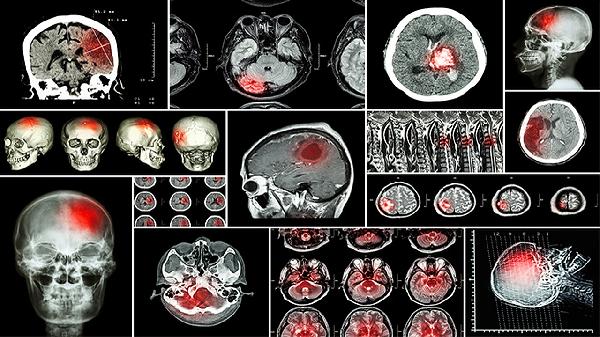

短暂性脑缺血属于急性脑血管事件,血栓或栓塞物暂时阻塞血管后自行溶解。典型表现为突发单侧肢体无力、言语含糊或视物模糊,症状通常在数分钟至1小时内消失,最长不超过24小时。尽管症状短暂,但约三分之一的患者可能在后续发生脑梗死。临床常用阿司匹林肠溶片、氯吡格雷片等抗血小板药物预防复发,严重者需进行颈动脉内膜剥脱术等干预。